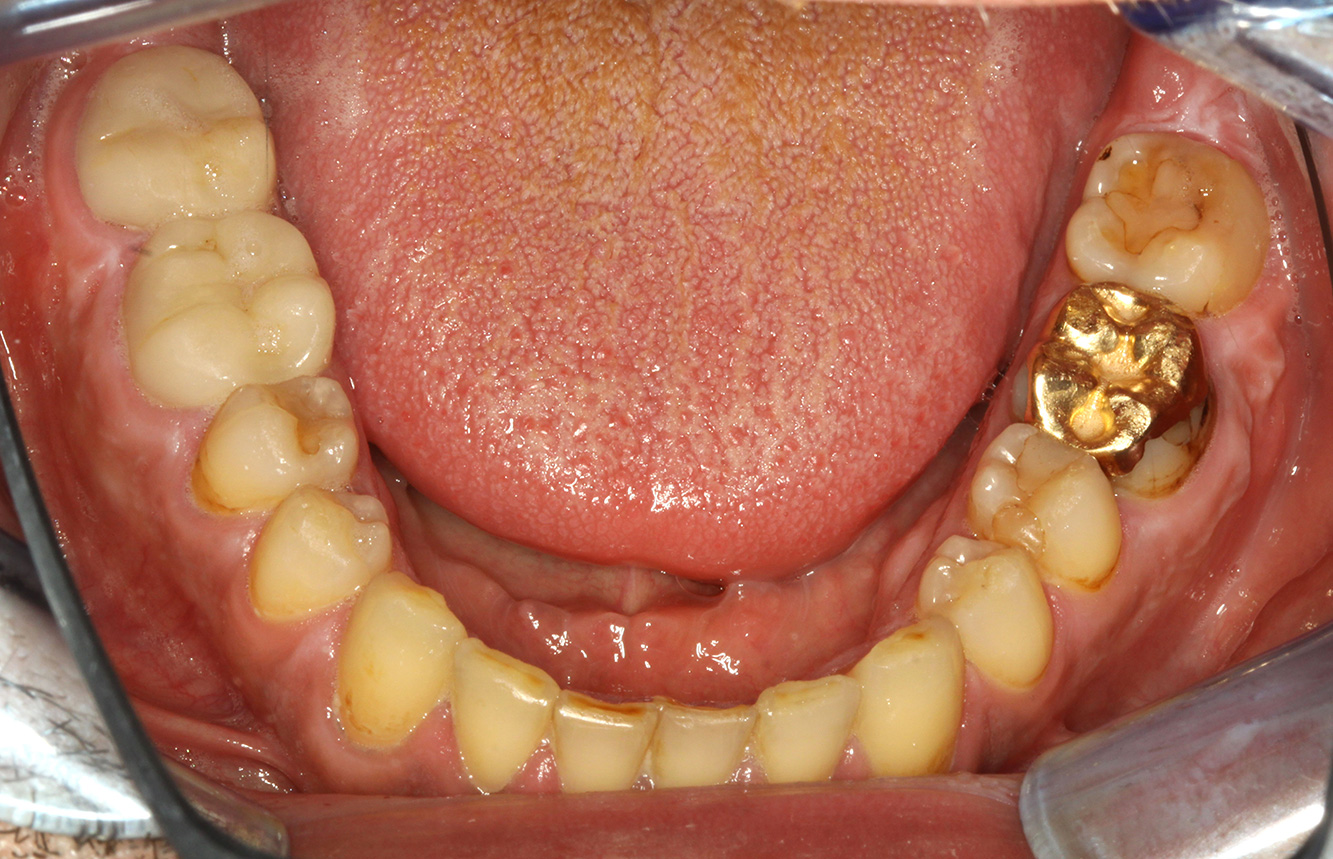

Il paziente ha 39 anni e in passato è stato sottoposto ad un intervento per la sostituzione della valvola aortica dovuta a insufficienza valvolare ed endocardite. Assume regolarmente l'ASS 100 come anticoagulante. Per quel che riguarda lo stile di vita, il regime alimentare seguito dal paziente è classificato come “dieta che favorisce la formazione della carie”, per via del consumo regolare di cibi ad alto contenuto di zuccheri e dei sei-sette pasti consumati al giorno. La salute orale del paziente indica un rischio moderato di carie, con lesioni attive. Il rischio di parodontite è basso, tuttavia il paziente è affetto da gengivite. Si formulano quindi i seguenti consigli per il trattamento di profilassi.

La sostituzione della valvola cardiaca e l'anamnesi di endocardite indicano un rischio aumentato di complicazioni. Al fine di ridurre il rischio di una nuova infiammazione, si deve consigliare una profilassi antibiotica (ad es. 2 g di amoxicillina un'ora prima della seduta). Nonostante la cura a lungo termine con un anticoagulante, non ci si aspetta un rischio aumentato di sanguinamento durante la seduta di profilassi.

Per la seduta di profilassi non si possono formulare consigli per strumenti specifici. Si può ricorrere a un'applicazione mirata di air-polishing e lucidatura con testina rotante per rimuovere delicatamente placca e discromie lungo i margini del restauro e per ridurre le nicchie dove i batteri cariogeni possono formare nuove colonie (19).

Si consiglia una fluorizzazione per stimolare ulteriormente la prevenzione della carie, prevenire in particolar modo nuove formazioni intorno ai margini del restauro e per sigillare le superfici radicolari. Entrambi i provvedimenti possono ridurre la sensibilità dei denti alla temperatura.

A causa delle lesioni cariose attive e del rischio ad esse associato di progressione, si consiglia un intervallo di richiamo ravvicinato di tre-quattro mesi.